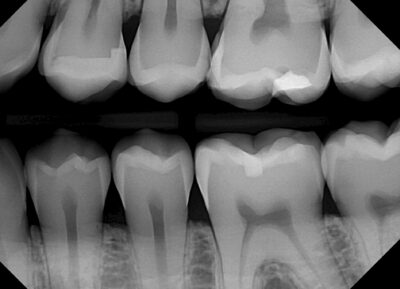

رادیوگرافی بایت وینگ یکی از ابزارهای حیاتی در دندانپزشکی برای ارزیابی وضعیت دندانهای ترمیم شده است. این نوع رادیوگرافی به دندانپزشکان کمک میکند تا با دقت بالا وضعیت ترمیمها را بررسی کرده و نقاط ضعف و مشکلات احتمالی را شناسایی کنند. با قرار دادن یک فیلم رادیوگرافی در دهان بیمار و گرفتن تصویر، دندانپزشک میتواند به راحتی سطح دندانهای ترمیم شده و نواحی اطراف آنها را مشاهده کند. این تصاویر نه تنها به تشخیص زودهنگام مشکلات کمک میکنند، بلکه به ارزیابی کیفیت ترمیمها نیز اهمیت میدهند. مطالعات نشان دادهاند که رادیوگرافی بایت وینگ به دلیل دقت بالا و توانایی نمایش جزئیات دقیق، بهویژه در نواحی خلفی دندانها، یک ابزار کلیدی برای تشخیص بیماریهای پریودنتال و تحلیل استخوان محسوب میشود.

در ارزیابی وضعیت دندانهای ترمیم شده، رادیوگرافی بایت وینگ قادر است نشانههای پوسیدگی جدید، عفونت یا شکستگیهای ممکن در ترمیمها را نمایان کند. این اطلاعات برای تعیین نیاز به درمانهای اضافی یا بازنگری در ترمیمهای قبلی بسیار حیاتی است. با توجه به اینکه برخی از مشکلات ممکن است در ابتدا قابل مشاهده نباشند، استفاده از این روش به دندانپزشکان این امکان را میدهد که از طریق مشاهده دقیق، بهترین تصمیمات درمانی را اتخاذ کنند.

ارزیابی وضعیت دندانهای ترمیم شده با رادیوگرافی بایت وینگ دارای تصاویر دقیق و واضح است

مزایای ارزیابی وضعیت دندانهای ترمیم شده با رادیوگرافی بایت وینگ بسیار چشمگیر است و این روش به عنوان یک ابزار کلیدی در دندانپزشکی به شمار میآید. یکی از مهمترین مزایا، توانایی این نوع رادیوگرافی در ارائه تصاویری واضح و دقیق از دندانهای ترمیم شده است. با استفاده از این تصاویر، دندانپزشکان میتوانند تغییرات کوچک و عیوب موجود را شناسایی کنند که ممکن است در معاینات بالینی عادی قابل مشاهده نباشند. این امکان باعث میشود تا درمانهای لازم به موقع و قبل از بروز مشکلات جدیتر انجام شود.